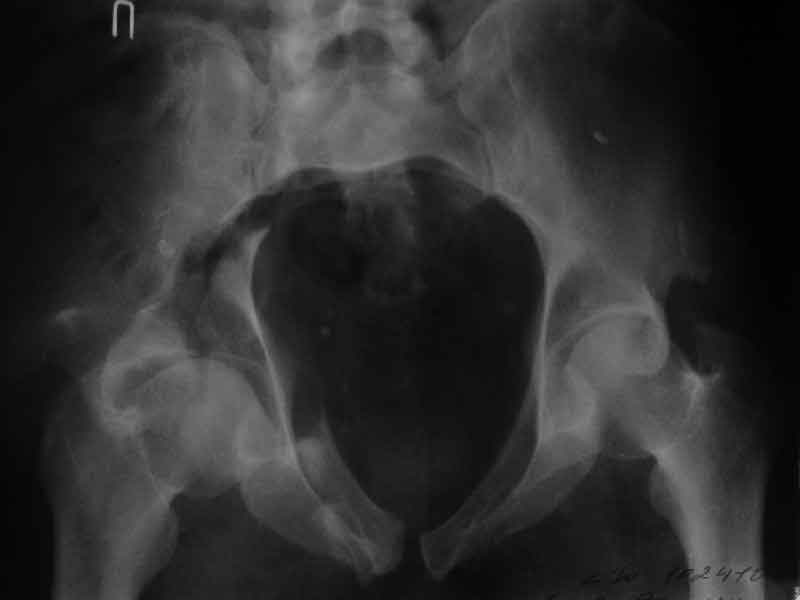

Дополнение, минимальный набор необходимых прекций, необходимых для лечения повреждений вертлужной впадины

Фас. Inlet

Подвздошная Запирательная